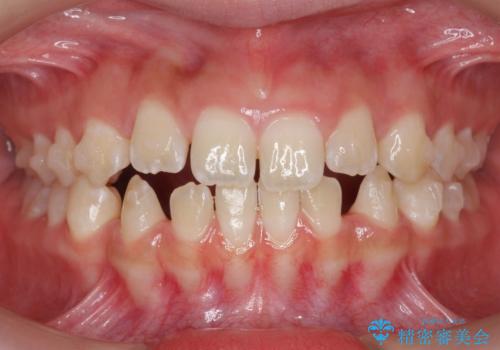

- 前歯の隙間を主訴に来院。

顎の大きさに比べて歯が小さく、隙間が目立っていました。

マウスピース矯正で隙間を閉じる処置を行いました。